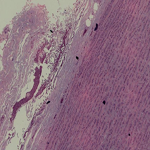

Human Aorta

The aorta is the largest artery in the body, originating from the left ventricle of the heart and extending down to the abdomen, where it branches off into two smaller arteries (the common iliacs). The aorta distributes oxygenated blood to all parts of the body through the systemic circulation.